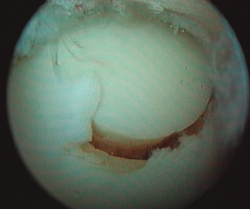

Figura 1. Lesión osteocondral de grado IIB en vertiente talar medial.

- Inicialmente procedemos a retirar el cartílago inestable, el hueso necrótico y la capa superior calcificada mediante un sinoviotomo, fresa motorizada, junto con instrumental de curetaje artroscópico (Figura 1).